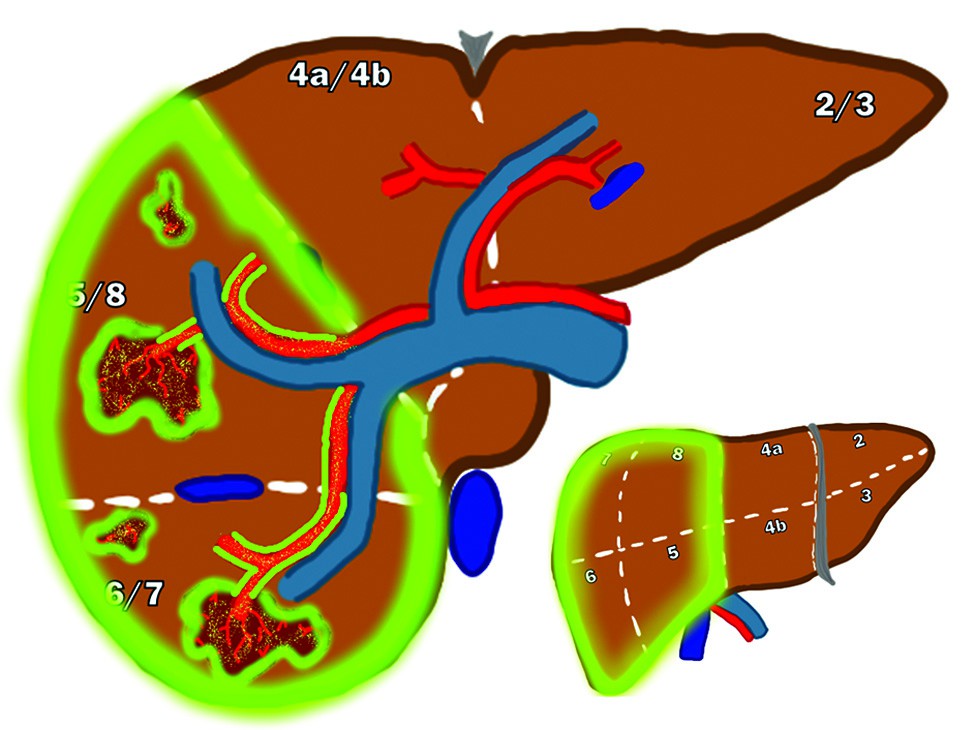

Un uomo di 62 anni con cirrosi alcolica Child-Pugh A e un carcinoma epatocellulare (HCC) di 8,2 cm che coinvolge i segmenti 5, 6, 7 e 8.

(a) Immagine di Risonanza Magnetica (MRI) con soppressione del grasso in fase arteriosa T1 di una lesione epatica confinata al lobo epatico destro. Il paziente era un potenziale candidato chirurgico, ma il fegato residuo futuro (FLR) era del 21% (lobo destro 1.562 mL e lobo sinistro + segmento 4 era 415 mL). Il volume del tumore era di 421 mL.

L'analisi dosimetrica con albumina macroaggregata di tecnezio-99m (Tc-99m MAA) (non mostrata) ha dimostrato un rapporto tumore-normale di 2,6 con una frazione di shunt polmonare (LSF) del 4,9%.È stata presa la decisione di eseguire una Y90-RL del lobo destro prescrivendo una dose MIRD all'angiosoma di 100 Gy. Sono state utilizzate microsfere di resina con 2 giorni di pre-calibrazione. Ciò ha portato a un'attività prescritta di 3,2 GBq (86,5 mCi).

(b) La SPECT/CT di Bremsstrahlung di ittrio-90 fusa ha dimostrato un assorbimento soddisfacente nel lobo destro. L'analisi dosimetrica post-Y90 (non mostrata) ha mostrato una dose al tumore di 172 Gy e una dose non tumorale di 66 Gy.

(c) La MRI con soppressione del grasso in fase arteriosa T1 a 3 mesi dal trattamento mostra una risposta tumorale parziale con malattia vitale residua e una lieve ipertrofia del lobo controlaterale. È stata presa la decisione di ripetere immediatamente la stessa dose MIRD prescritta all'angiosoma di 100 Gy con microsfere di resina con 2 giorni di pre-calibrazione.

(d, e) La SPECT/CT di Bremsstrahlung di ittrio-90 fusa assiale e coronale dimostra nuovamente un assorbimento soddisfacente nel lobo destro.

(f) La MRI con soppressione del grasso in fase arteriosa T1 a 3 mesi dal trattamento mostra una risposta tumorale completa con significativa ipertrofia del lobo controlaterale (ipertrofia del lobo sinistro del 77% [da 415 mL originari a 736 mL finali]). Non sono stati osservati eventi avversi clinicamente significativi.